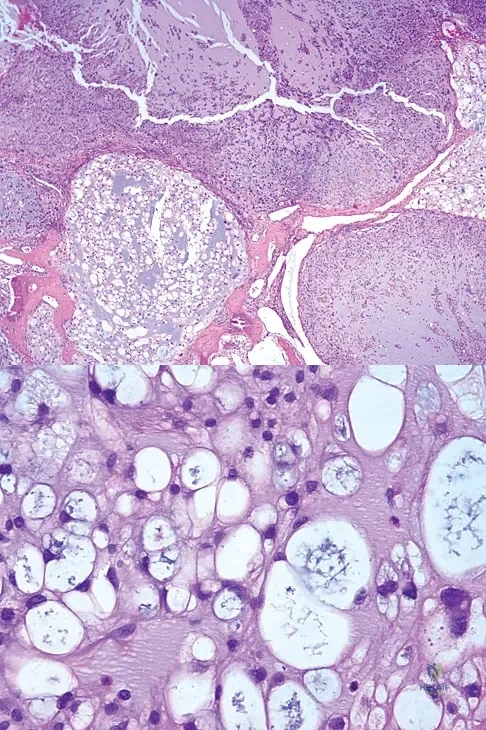

The biopsy specimens seen in Figures 55a and 55b are from a lytic lesion in the sacrum of a 58-year-old man. What is the most likely diagnosis?

Explanation